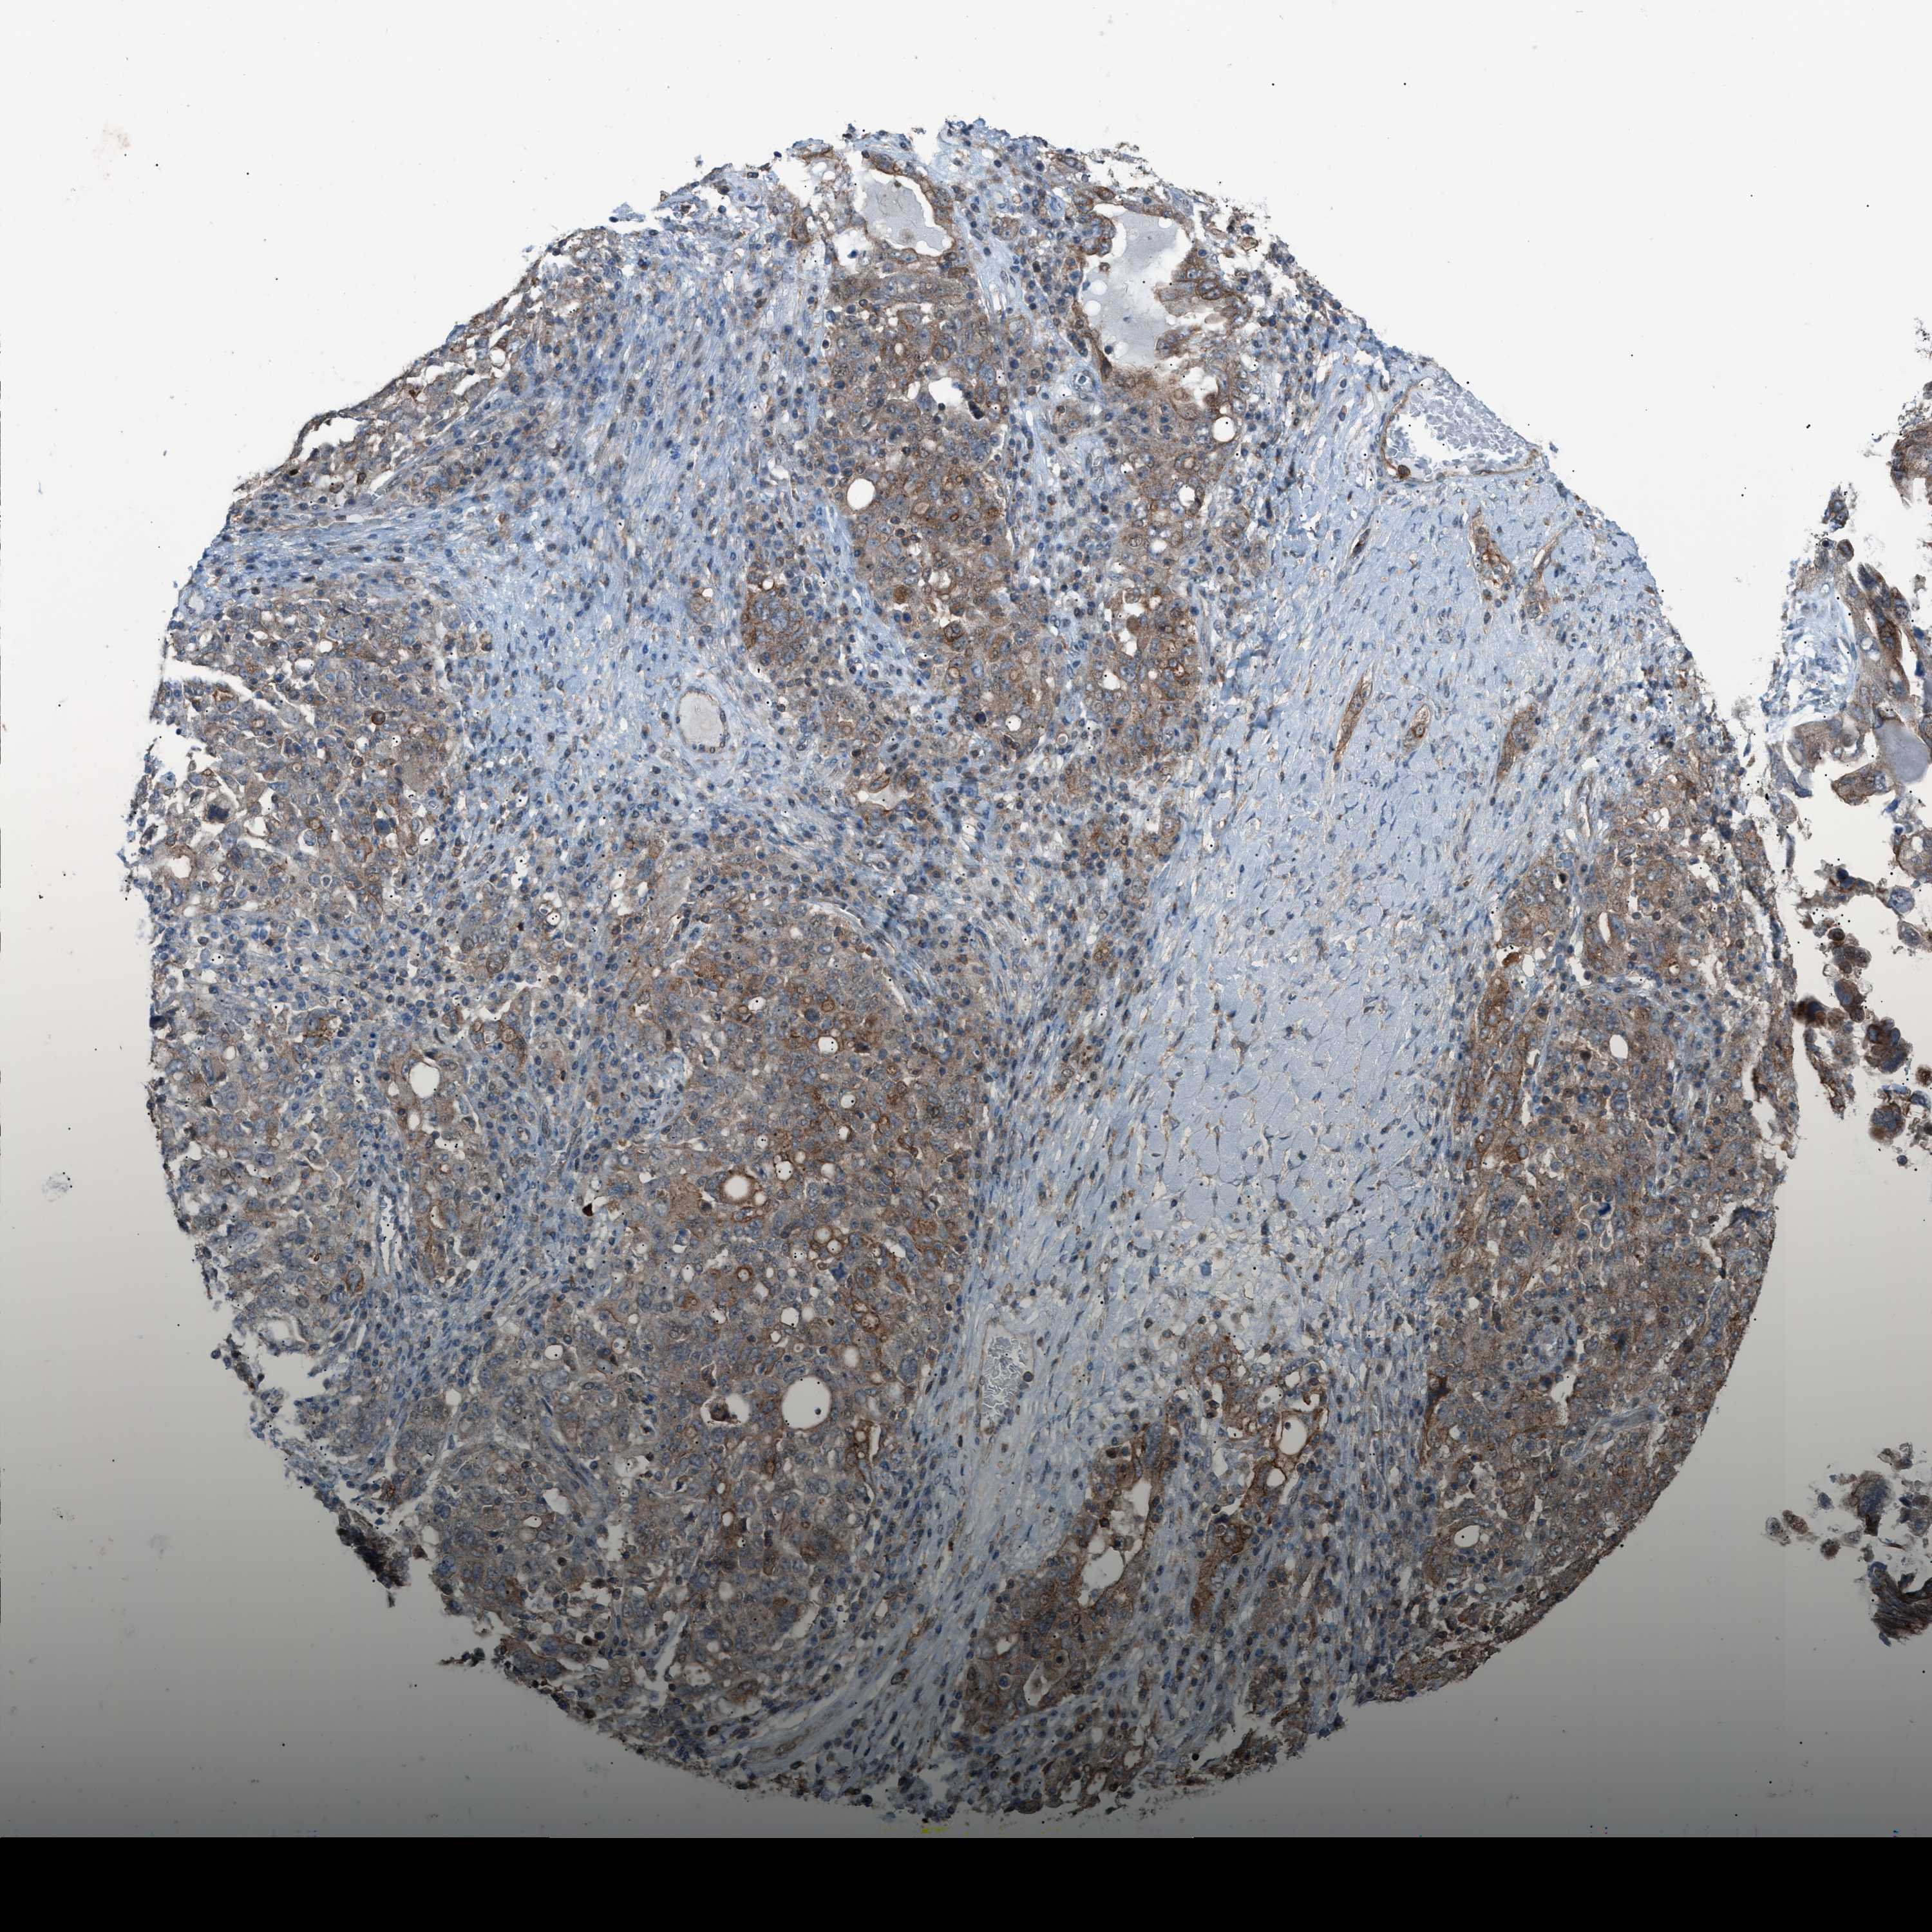

OVARIAN CANCER - Protein expressioni

A mouse-over function shows sample information and annotation data. Click on an image to view it in a full screen mode. Samples can be filtered based on level of antibody staining by selecting one or several of the following categories: high, medium, low and not detected. The assay and annotation is described here.

Note that samples used for immunohistochemistry by the Human Protein Atlas do not correspond to samples in the TCGA dataset.

Antibody stainingi

Antibody staining in the annotated cell types in the current human tissue is reported as not detected, low, medium, or high, based on conventional immunohistochemistry profiling in selected tissues. This score is based on the combination of the staining intensity and fraction of stained cells.

Each image is clickable and will lead to virtual microscopy that enables deeper exploration of all samples and also displays staining intensity scores, fraction scores and subcellular localization as well as patient and tissue information for each sample.

Antibody HPA015323

Antibody HPA015810

Carcinoma, endometroid

Cystadenocarcinoma, serous, NOS

Cystadenocarcinoma, mucinous, NOS

Carcinoma, NOS